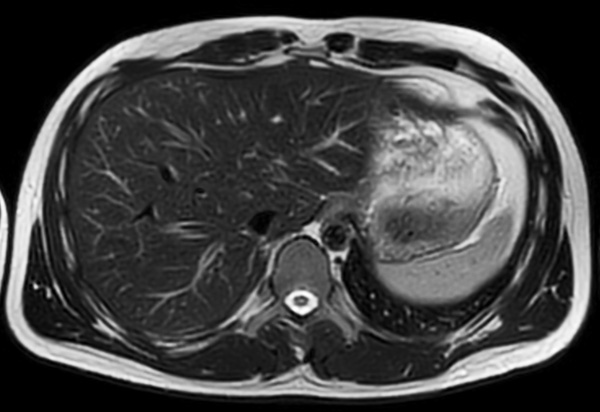

Axial T2w MultiVane XD SPIR (fast)